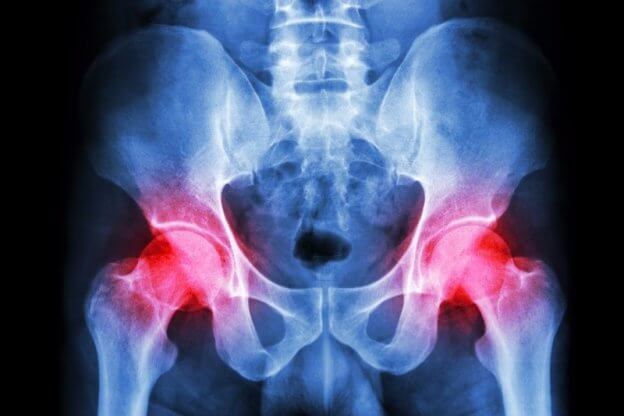

I’m not sure whether it is referred pain from my back. Or whether it was caused by sitting in the vehicle for 6+ hours per day. But now my right hip is so painful. I don’t think I have damaged it. But I cannot put any weight on my leg and have hobbled around taking tiny steps to get around. The pain seems to radiate down my leg and is excruciating. So have detoured to a larger city on our way home to see a chiropractor on Monday morning before undertaking the last 1000 kilometer trip home.

Late November my left hip area just to the outer edge of my hip bone became sore. Then, the skin flushed a pinkish purple and the flushed area is about the size of four quarters. Also, there is a sort of dent in the tissue.

Today I wondered about “gout”. I’ve had gout in my toe 4 times several years ago. I also had pseudo-gout in my ankles about 9 years ago. The tissue near the flushed area is sore. The tissue also appears to have a slightly sunken area to it but today it doesn’t appear to be sunken much, yet flushed and sore. Flushed skin is smooth, no sores or rash and it doesn’t itch yet it is not as excruciating as I remember the pain being on my red toe when I had gout there years ago.

My hip joint feels like bursitis has started over and my sacroiliac appears to be flared again as the hot spots of pain go down my left leg. This is not keeping me from daily activities but it is always there. I wish I could get this resolved. Also, I wrecked a motorcycle 40 years ago and landed on my left hip which is the reason for recurring bursitis.